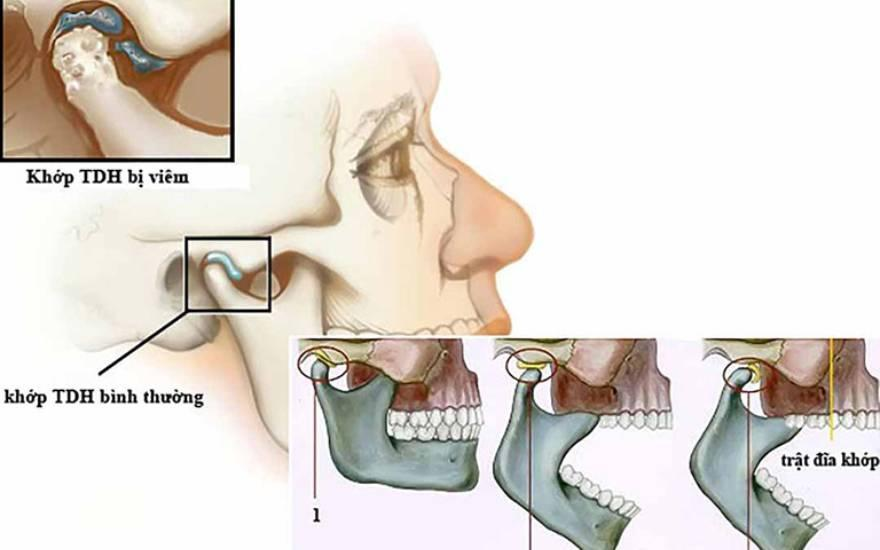

Ảnh 1: thời gian hồi phục TMJ

Ảnh 2: mức độ TMJ